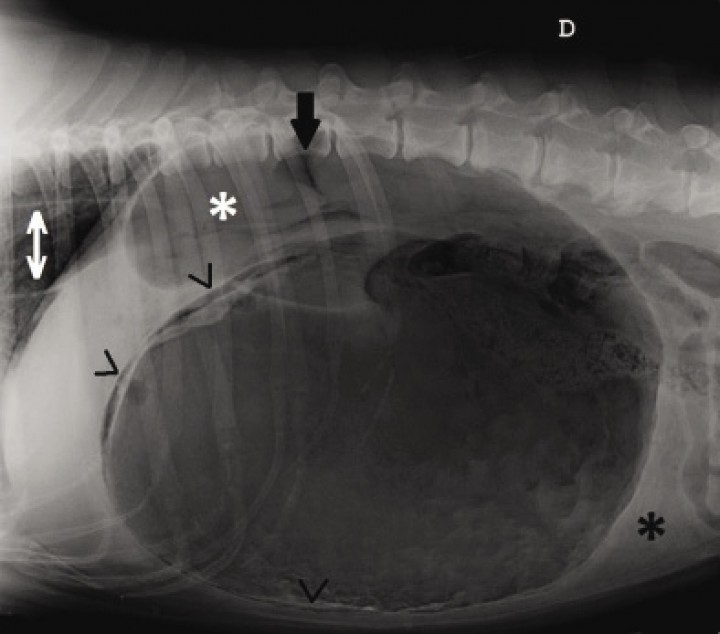

Se observa una severa distensión gástrica, con desplazamiento dorsocaudal de vísceras abdominales (zona retroperitoneal y paquete intestinal, respectivamente) e hígado hacia craneal. El píloro se encuentra en la zona dorsocraneal del abdomen, mostrándose separado del cuerpo gástrico por una línea de compartimentalización. No se visualiza el bazo en esta proyección, pero sin embargo, hay pérdida de definición peritoneal en la zona ventrocaudal al estómago, así como aumento de definición en la zona dorsocraneal del abdomen superpuesta con el píloro. En la porción de tórax incluida en el estudio se distingue una dilatación de esófago caudal, que continúa caudalmente hasta su entrada en estómago. Se puede apreciar con claridad la presencia de gas intramural en prácticamente la totalidad de la pared gástrica, principalmente en zona de fundus y cuerpo gástrico, sin apenas visualizarse con claridad en la zona pilórica. Este gas muestra un patrón lineal, pero presenta una pared irregular, sin distribuirse de la misma manera en todo su recorrido. Espondiloartrosis L3-L4 y L4-L5. El resto de estructuras abdominales aparecen dentro de los límites normales (Fig. 2).

<p>Misma imagen que la Figura 1. Se observa una severa distensión gástrica, píloro en zona dorsocraneal (asterisco blanco), dilatación esofágica (flecha doble blanca), falta de definición peritoneal (asterisco negro), aumento de contraste abdominal en zona dorsocraneal (flecha negra) y presencia de gas intramural (puntas de flecha negras).</p>

Figura 2

Misma imagen que la Figura 1. Se observa una severa distensión gástrica, píloro en zona dorsocraneal (asterisco blanco), dilatación esofágica (flecha doble blanca), falta de definición peritoneal (asterisco negro), aumento de contraste abdominal en zona dorsocraneal (flecha negra) y presencia de gas intramural (puntas de flecha negras).

Estos hallazgos son consistentes con una dilatación y torsión gástrica de aproximadamente 180 grados, con neumatosis gástrica y megaesófago secundario a aerofagia, así como presencia de líquido libre y posible neumoperitoneo.